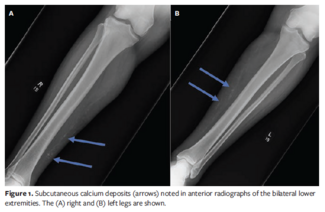

The author describes 3 cases of nonuremic calcific arteriolopathy successfully managed with multimodal treatment including wound hygiene, pain management, and infection control.